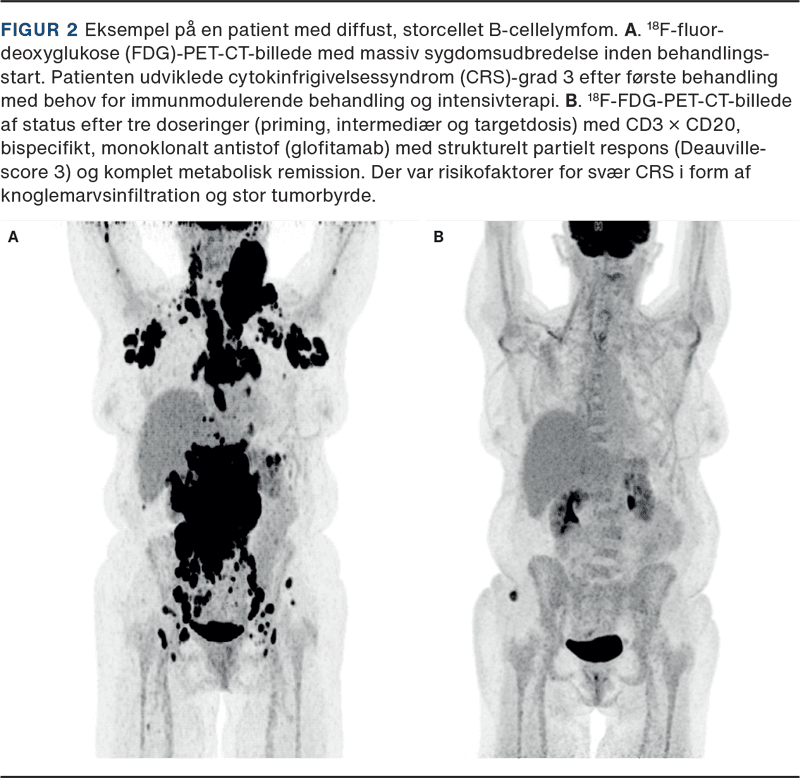

Figur 2 viser et eksempel på en ældre patient med udbredt, diffust, storcellet B-cellelymfom før og efter behandling med TCE. Patienten udviklede dag et – allerede to og en halv time efter behandling med startdosis glofitamab (TCE) – feber og takykardi og blev givet første dosis tocilizumab. I dette døgn havde patienten fortsat feber og hypotension på trods af gentagne tocilizumab- og dexamethasonbehandlinger. Patienten blev overflyttet til intensivafdeling med CRS-grad 3 til behandling med noninvasiv ventilation, vasopressorstoffer og monitorering. Patienten stabiliseredes og kunne planmæssigt modtage intermediær dosis glofitamab på ottendedagen, som var veltolereret med beskedne bivirkninger i form af CRS-grad 1, hvilket illustrerer den øgede risiko for CRS ved de(n) først(e) dosering(er).